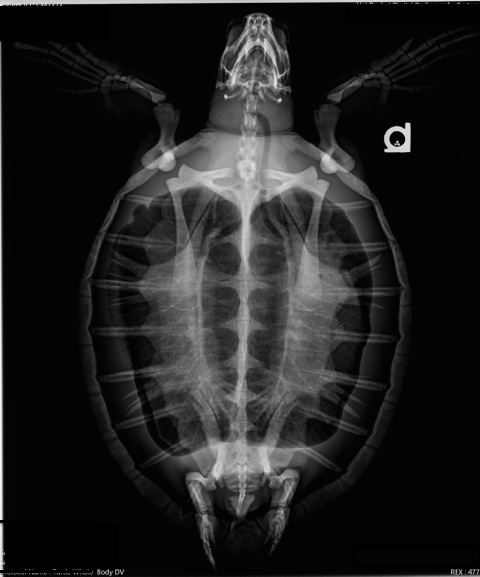

Ideally, horizontal beam radiographs are used to evaluate buoyancy disorders. CT scan and MRI are also valuable imaging tools if available.

- Pneumocoelom (free gas in the body cavity) is seen associated with trauma that can result in lung tears. The presence of free gas in the coelom will create positive pressure and compress other viscera including the lungs. Many small lung tears will spontaneously seal. Daily aspiration of free gas (measure and record the volume) can promote sealing of small tears.

Pneumocoelom on left due to carapace fracture with ileus on right

- Pneumocoelom is often central and typically does not shift from side to side.